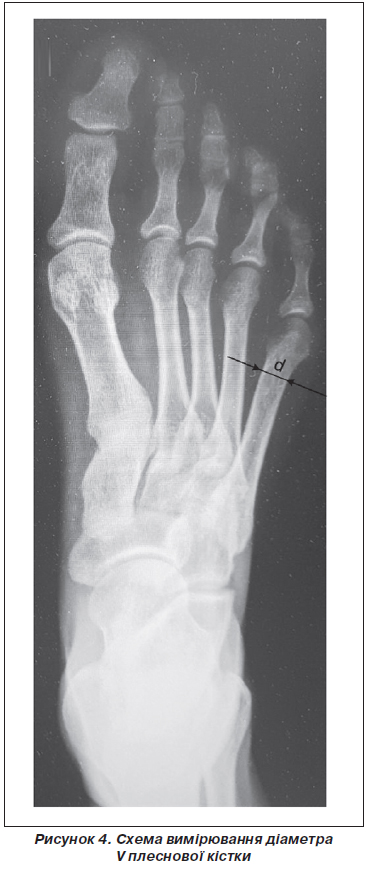

Для визначення варіації товщини V плеснової кістки у дистальному відділі було оброблено 39 цифрових рентгенограм стоп пацієнтів. Схема вимірювання наведена на рис. 4.